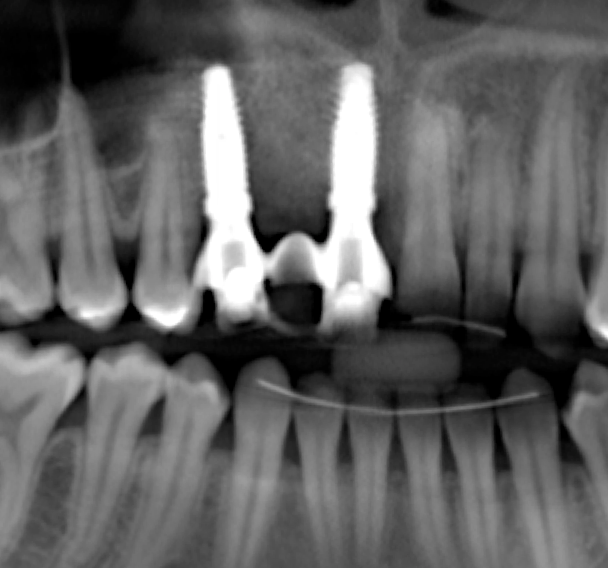

Tomographic images revealed a large tridimensional defect, with vertical and horizontal loss of bone extending to the apical third of teeth Nos. 6 and 8. Additionally, a buccal bone dehiscence was evident on tooth No. 5, and thin labial plates secondary to the orthodontic movement were present in several areas (Figure 3 and Figure 4).